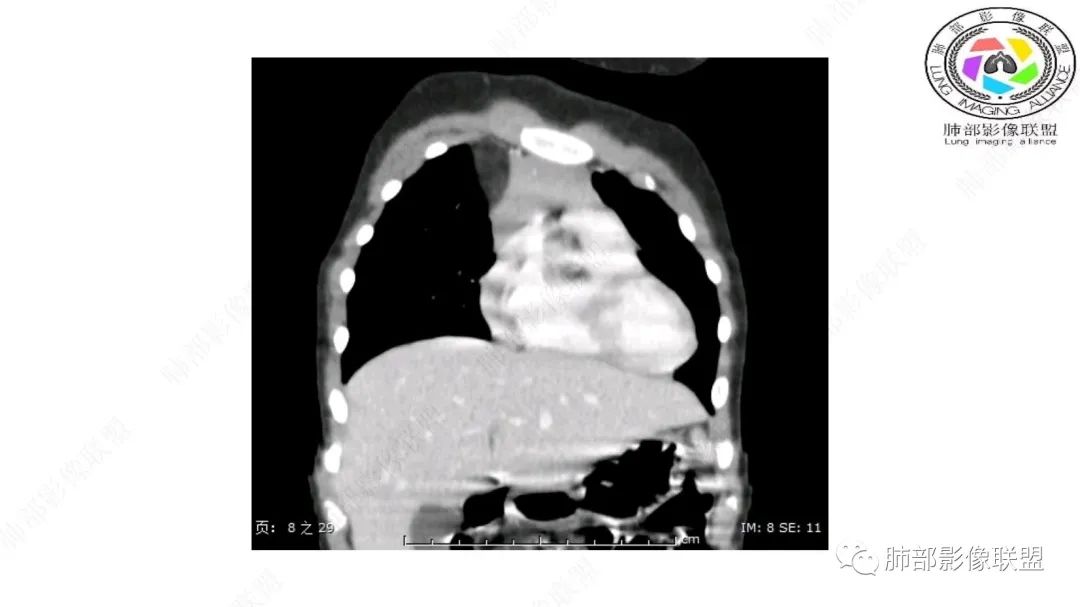

前方突入胸壁

有高密度影,有其他的血管来源。

病灶属于交界区,主体位于肺内,占位效应明显,前方突入胸壁,胸腺受压变形,胸膜显示欠清楚;病灶包绕上叶肺动脉;似乎有体动脉供血。符合肺内的点:包绕上叶肺动脉分支;符合纵隔的点:前方似乎突入胸壁,与胸腺关系比较密切,但是与上腔静脉的关系提示病灶不支持纵隔来源,前纵隔的常规会将上腔静脉受压后移、外移,这是不符合的。

从这个角度符合肺内的,有一点不太踏实的是:似乎突入前胸壁。

1.右上肺-纵隔交界区巨块影,主体位于右肺一侧,紧贴胸腺、头臂干、右锁骨下动脉、上腔静脉、奇静脉等,不能分离,但病灶整体边界清楚。注意上述相邻腔静脉等结构未见受压变形,纵隔亦未见明显向左推移,至少提示两点:

1)病灶相当柔软。

2)位于纵隔内或纵隔胸膜的可能性较小,因为受纵隔胸膜反作用力影响不明显。

2.肺动脉穿行也许是肺内来源最重要支持点!